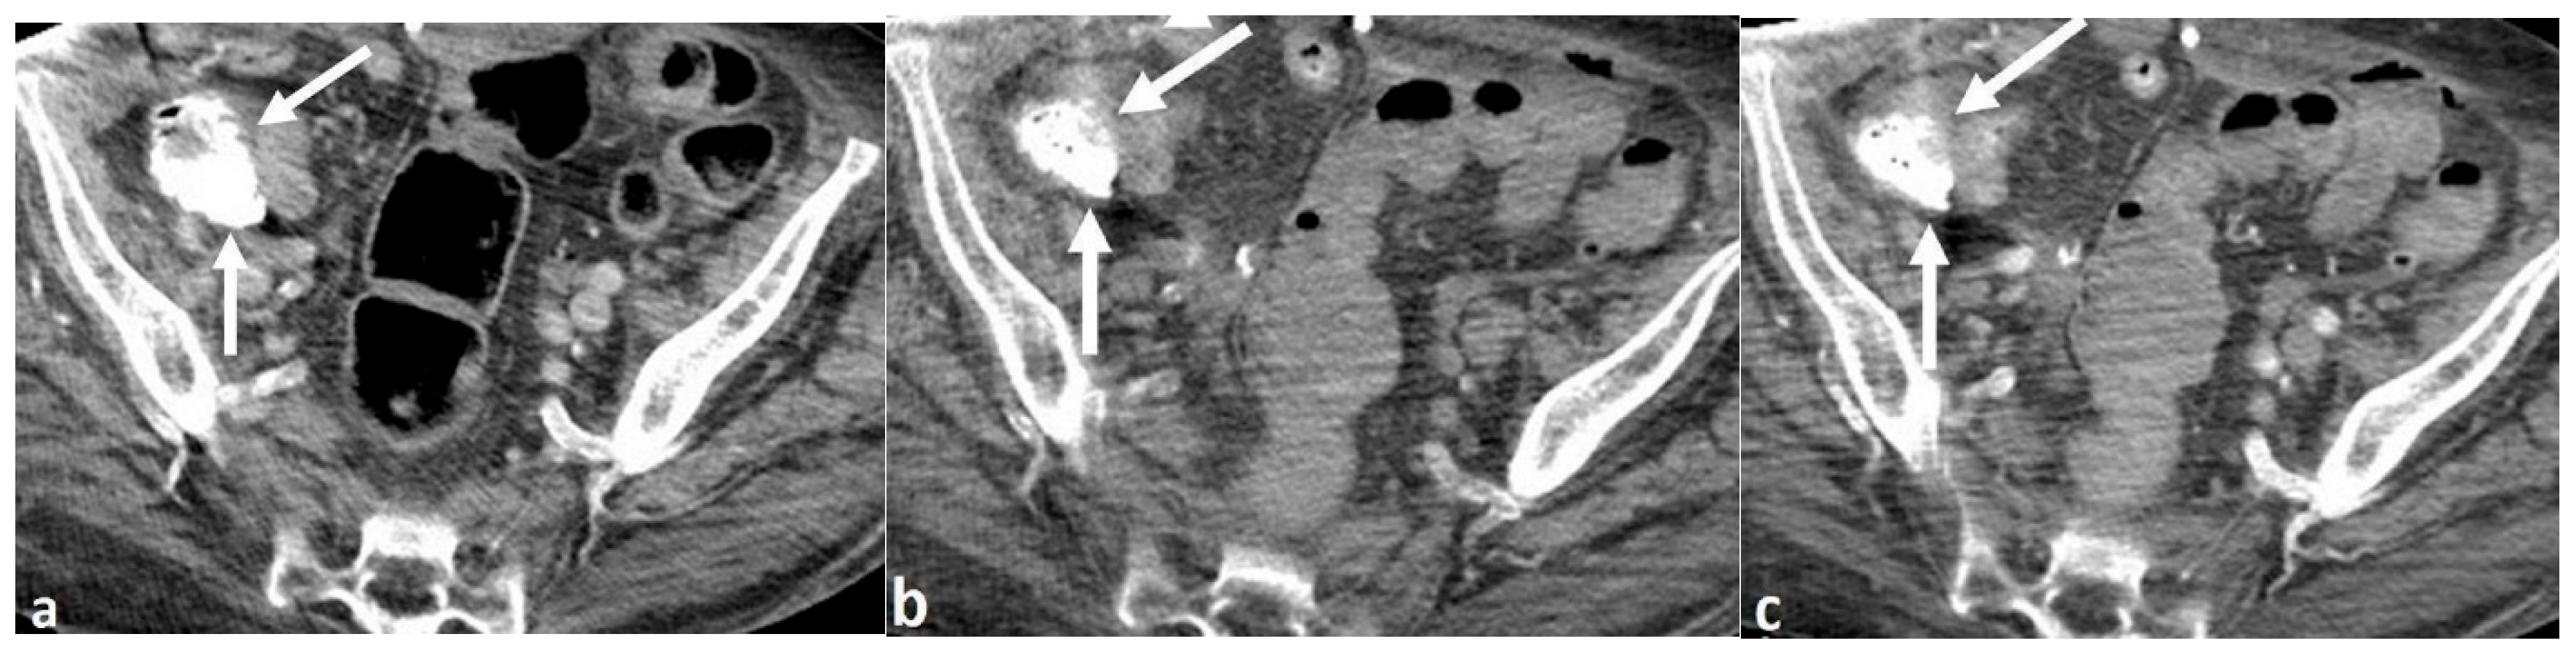

Sodium Zirconium Cyclosilicate in the Gastrointestinal Tract Mimicking an Acute Gastrointestinal Bleed on CT